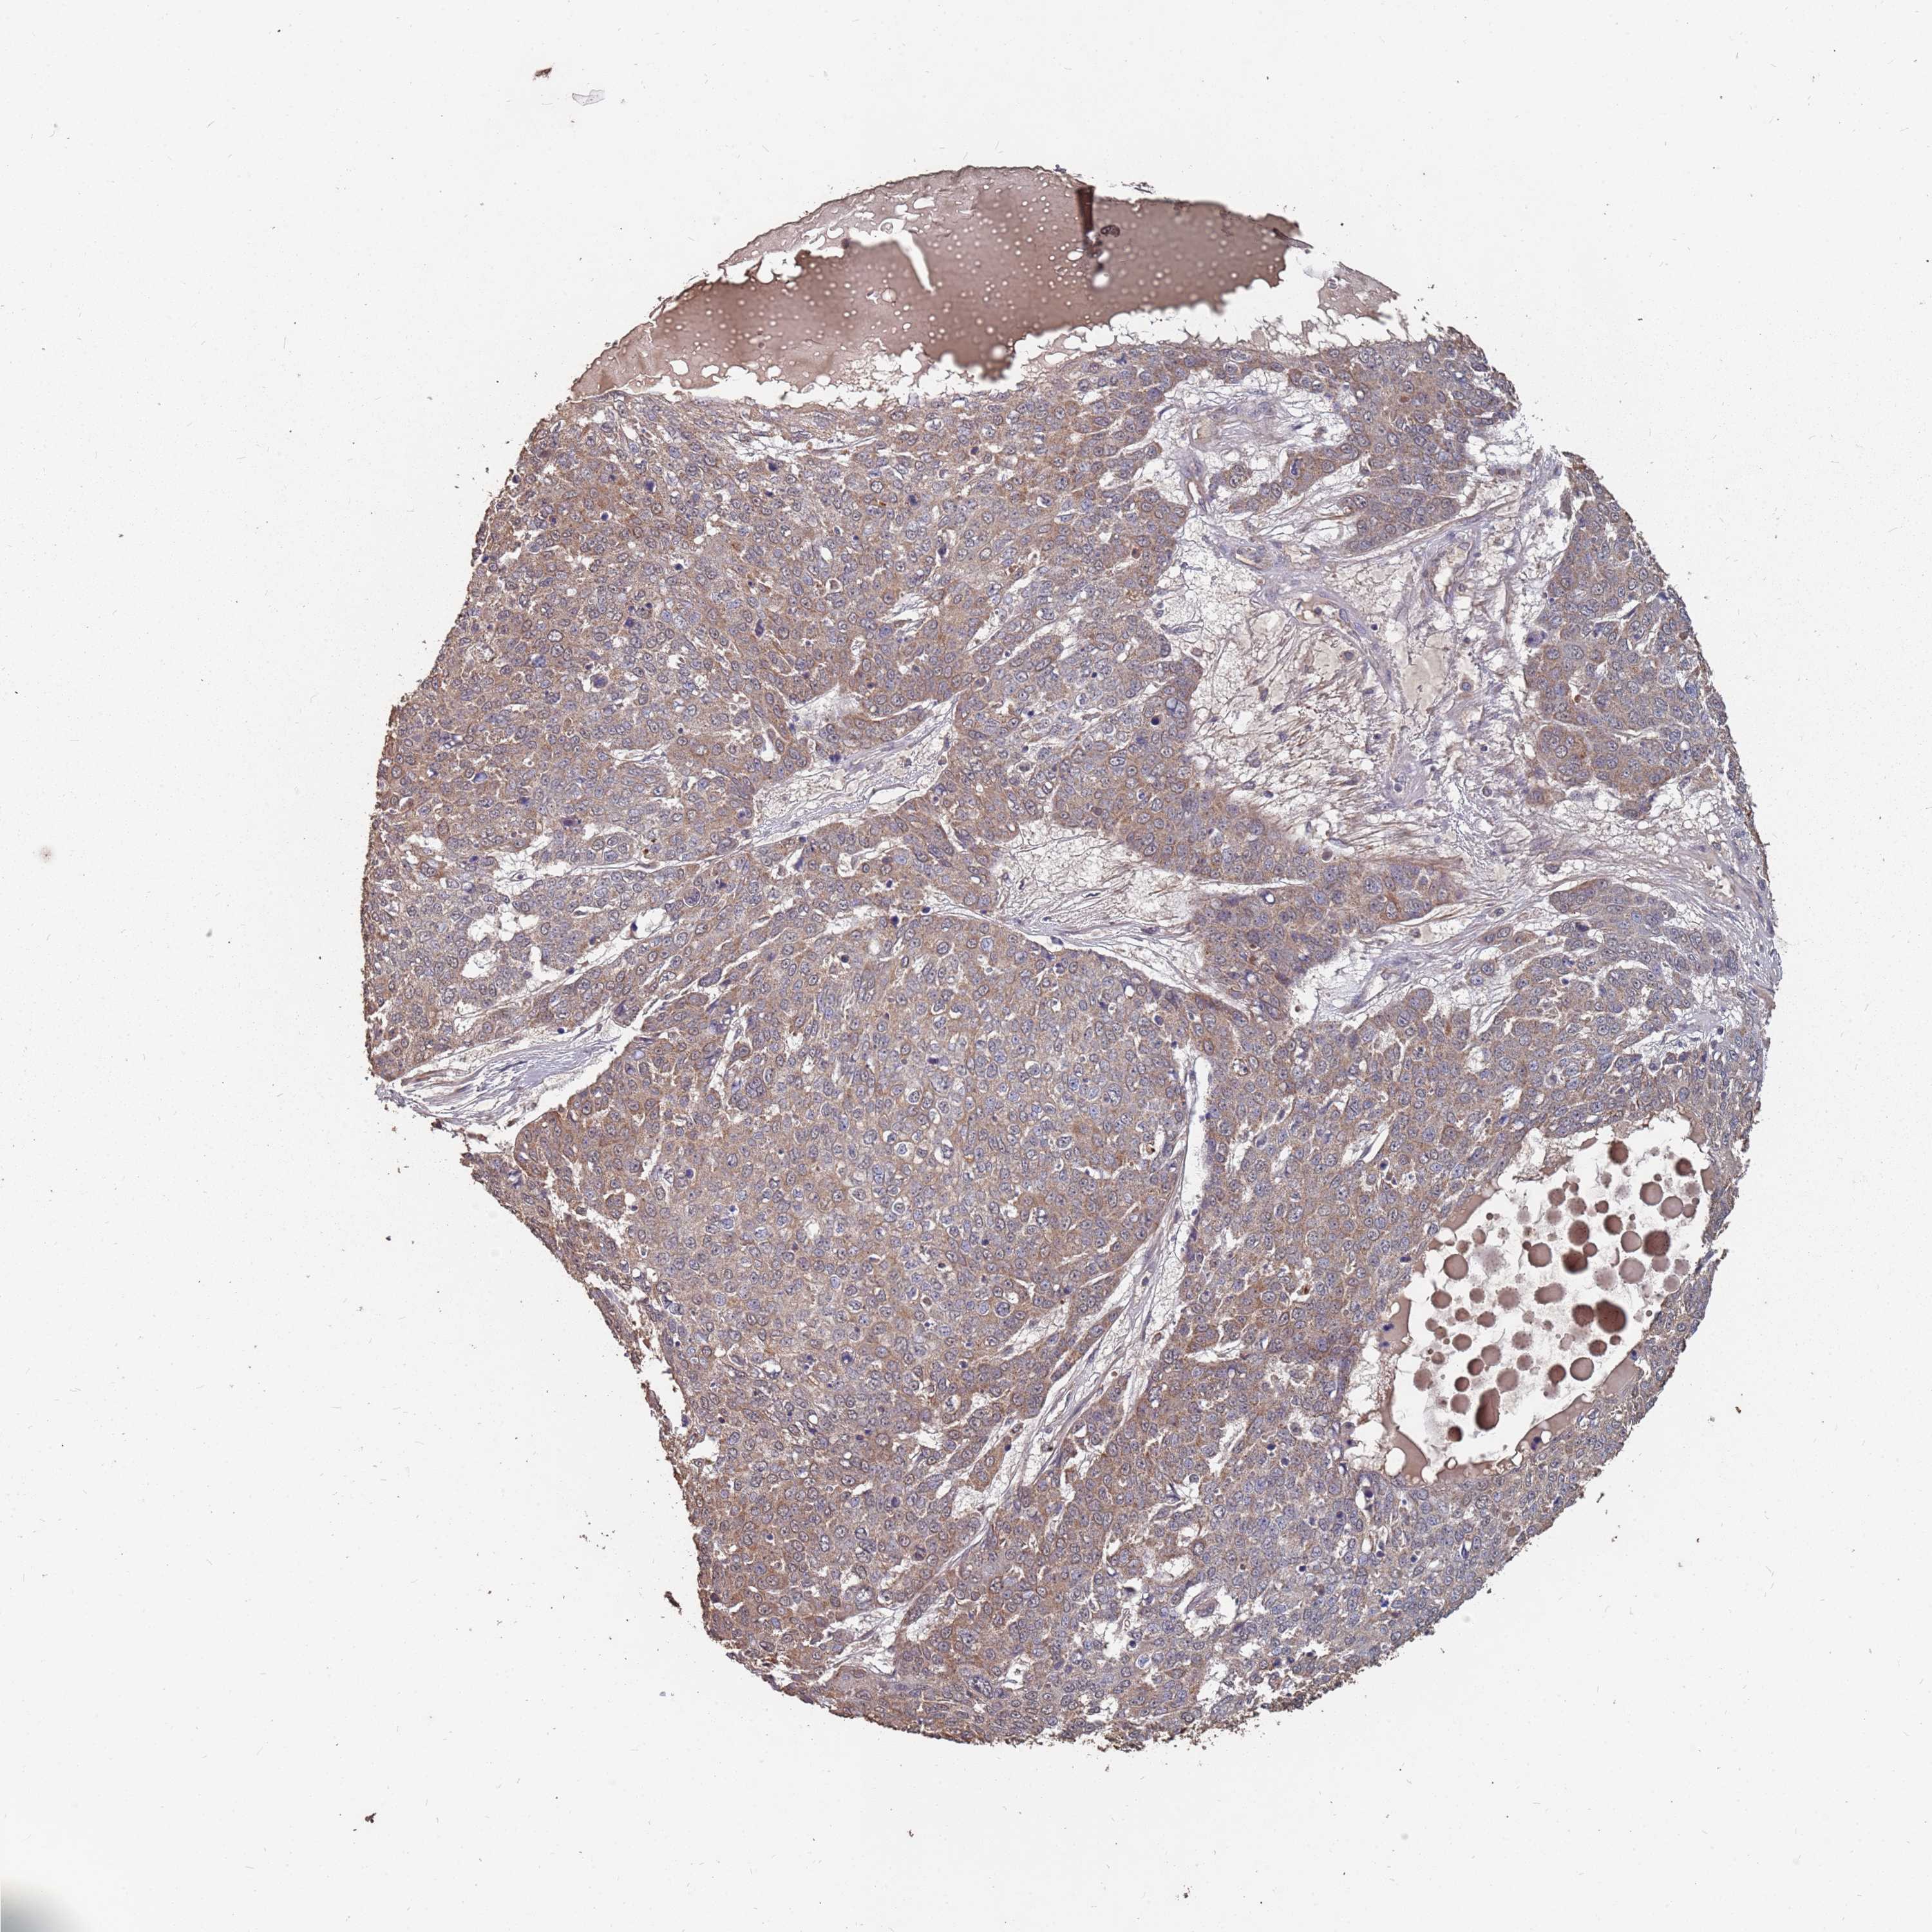

SKIN CANCER - Protein expressioni

A mouse-over function shows sample information and annotation data. Click on an image to view it in a full screen mode. Samples can be filtered based on level of antibody staining by selecting one or several of the following categories: high, medium, low and not detected. The assay and annotation is described here.

Antibody stainingi

Antibody staining in the annotated cell types in the current human tissue is reported as not detected, low, medium, or high, based on conventional immunohistochemistry profiling in selected tissues. This score is based on the combination of the staining intensity and fraction of stained cells.

Each image is clickable and will lead to virtual microscopy that enables deeper exploration of all samples and also displays staining intensity scores, fraction scores and subcellular localization as well as patient and tissue information for each sample.

Antibody HPA020459

Basal cell carcinoma

Squamous cell carcinoma, NOS

Squamous cell carcinoma, metastatic, NOS